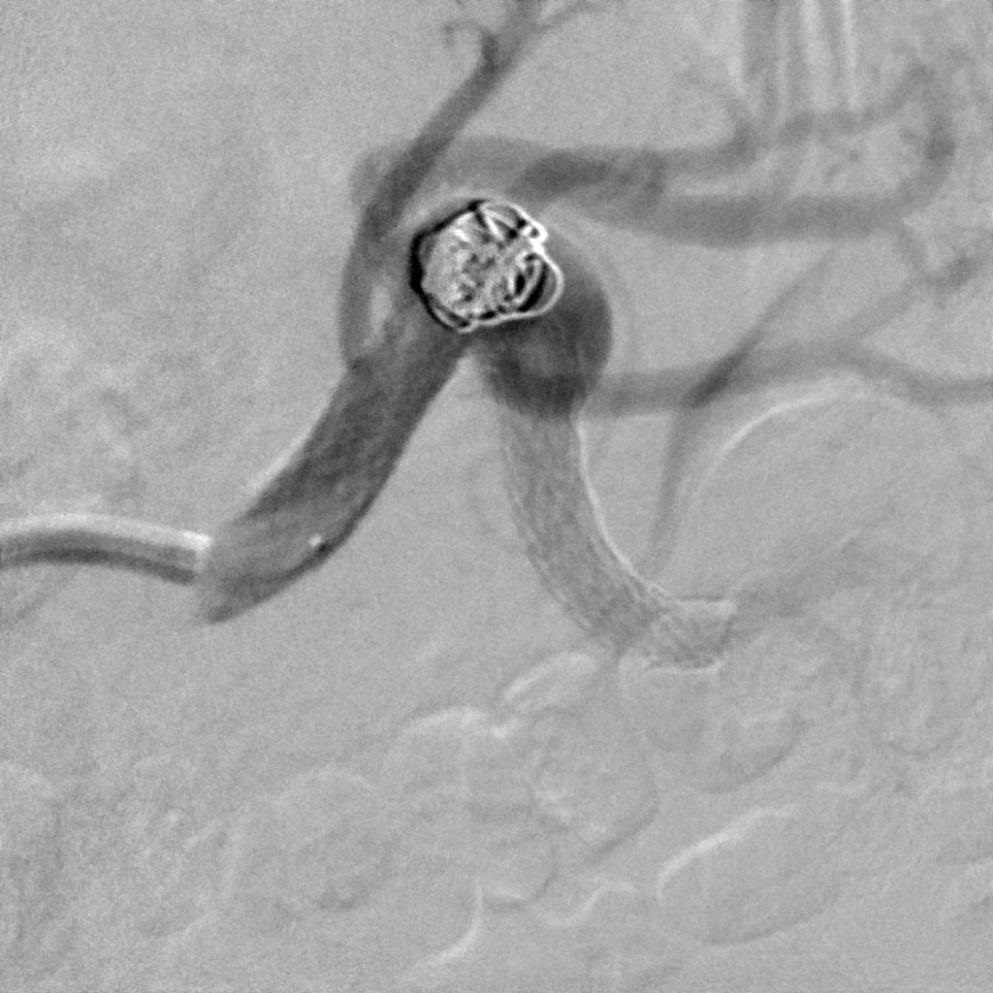

释放完成后造影显示载瘤动脉远端内血栓。 泵入肝素一天后复查造影,血栓消失。与术前比较少了一支肾后段的动脉。

CTA提示窄颈动脉瘤,瘤囊上有肾动脉分支 血管造影证实瘤囊上分支

支撑架辅助弹簧栓子瘤囊填塞 最后一枚弹簧栓子逸出支撑架,并收回重新释放

瘤囊填塞后 瘤囊上分支闭塞